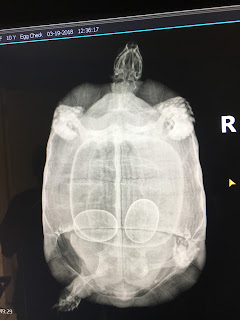

The owners were concerned that she may have been "egg-bound" because this breed of tortoise generally lays 3 eggs. To determine if she was harboring any more eggs, we took radiographs of her which revealed she had 2 eggs yet inside! After consulting with an exotic vet specialist, she was deemed healthy and the owners were made aware that it may take up to 3 months for "Georgie" to lay the remaining eggs. Unfortunately, "Georgie" is an only-tortoise-child, so her eggs are unfertilized and have no embryo.